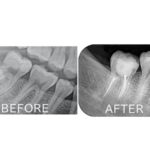

当院の精密根管治療 では、根管治療に精通した日本顕微鏡歯科学会認定医が十分な時間をかけて診療しております。また、様々な機器、薬剤を用いて、患者様の大切な歯をできる限り残すための環境を整えております。

当院では必要に応じて、保険診療であってもマイクロスコープを使って根管治療を行います。視野を拡大した細かい作業のため時間はかかりますが、再発を抑えて長期的にご自身の歯を使用できるような治療を心がけております。